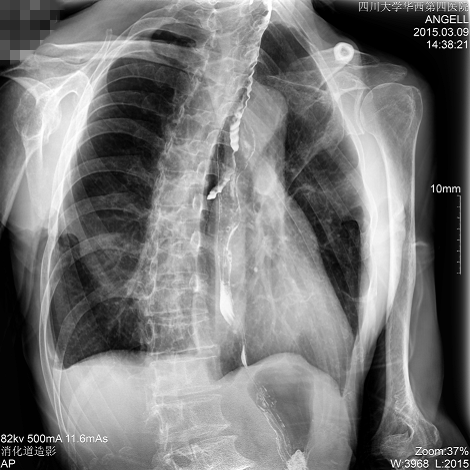

如下圖所示:該患者因吞咽時感到很難受,進食時也經常咳嗽故就醫診斷。華西醫院醫生使用動態DR為病人進行消化道造影診斷,要求他吞鋇后發現,食道各段通過順利,形態規則,雙側梨狀窩不對稱左側稍淺,多次吞咽動作后,仍見鋇劑滯留,并見鋇劑進入氣管,屬于會厭征陽性。會厭功能紊亂,鋇劑進入了氣管。

圖為斜位:通過動態影像可以清楚看到鋇劑進入了支氣管道